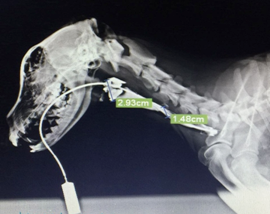

Figure 6

Contrast radiography-Narrowing of Esophageal lumen